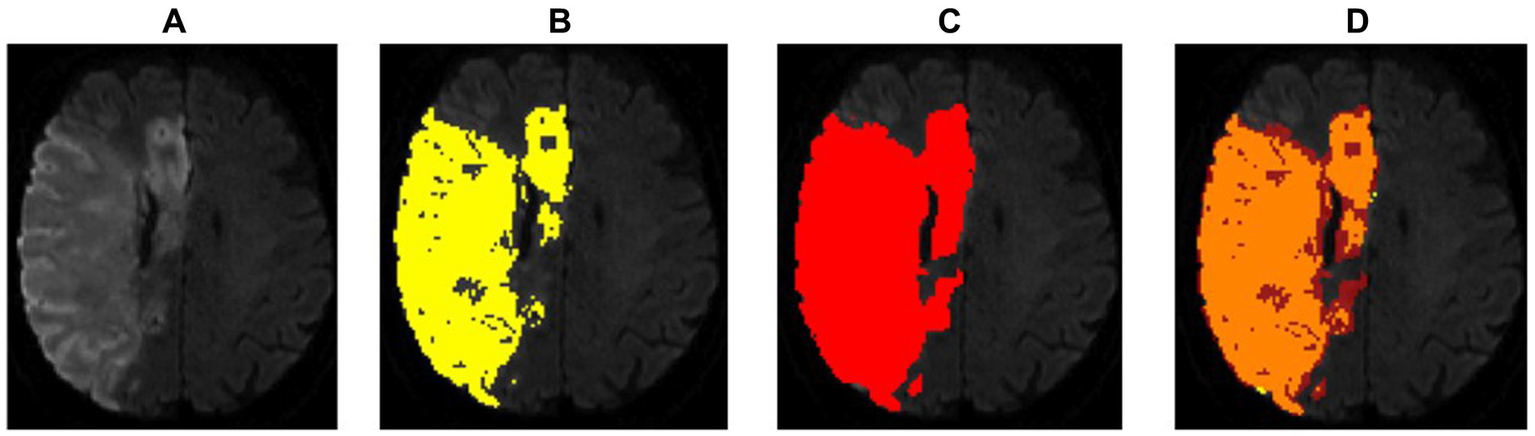

Figure 2 shows an example of a successful segmentation of both lesion types in one patient, and Table 1 summarizes the baseline demographic characteristics of participants for both cohorts.

Figure 2

Example of an optimal segmentation of the program compared to the ground truth. The patient had a proximal M1 occlusion on the right side and suffered an infarction of the basal ganglia and the frontal operculum. The diffusion segmentation is shown above on TraceW maps, perfusion can be viewed below on Tmax maps thresholded to 6 s. The diffusion and perfusion segmentation are not displayed in the same slice. DSC for diffusion was 0.87 with an overestimation of the lesion size by the program of 9.63 mL. For perfusion, the dice score was even higher at 0.94, whereby the StrokeSegApp underestimated the deficit slightly by 4.37 mL. Following the DEFUSE 3 criteria, the approaches came to the same conclusion that a mechanical thrombectomy is not indicated because the penumbra is too small. (A) Blank scan used for segmentation, (B) ground truth ROI, (C) StrokeSegApp ROI, and (D) both ROI superimposed, whereby orange indicates areas of overlapping mapping, yellow shows areas missed by the StrokeSegApp and red displays diffusion/perfusion deficits overestimated by the application.